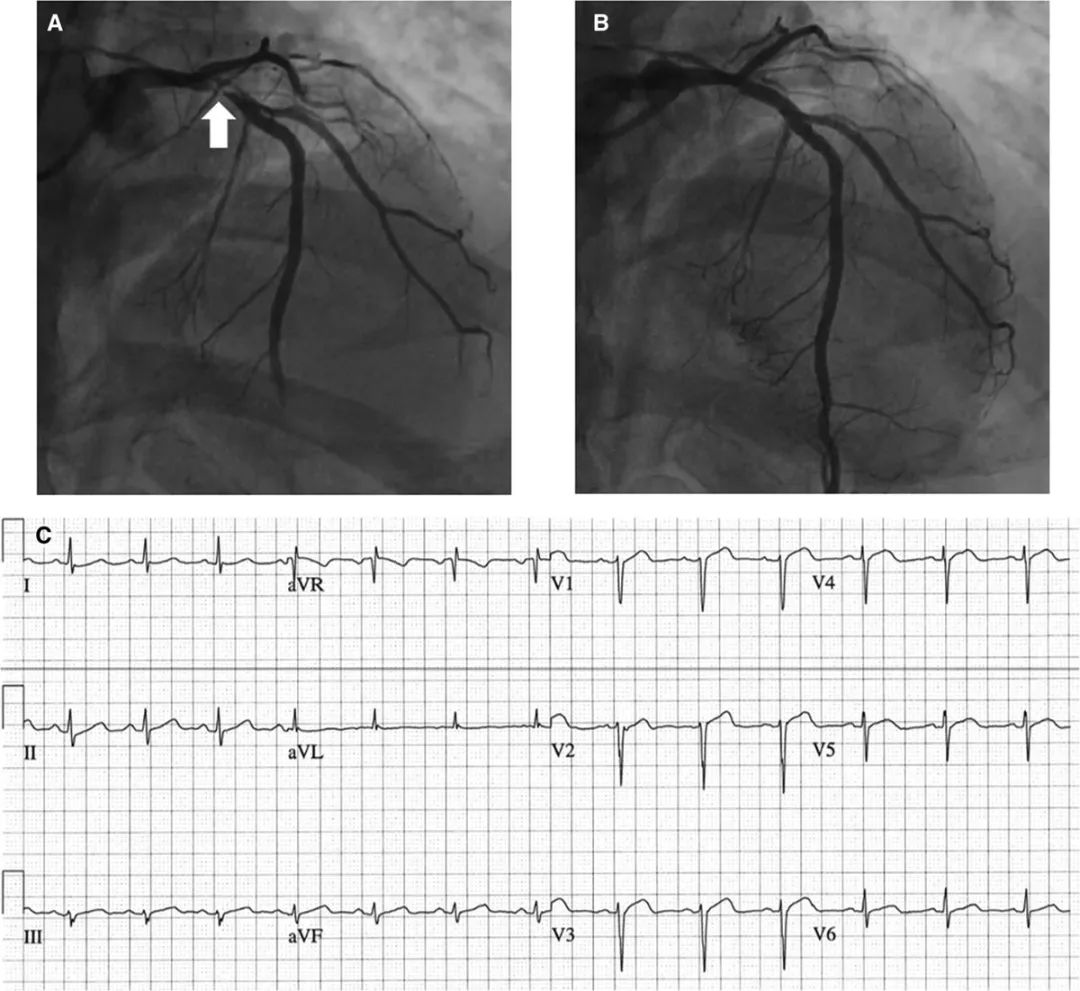

急诊冠脉造影显示,左前降支近端次全闭塞,伴TIMI 2级血流,如图2A。置入药物洗脱支架(4.0×18 mm)后,恢复TIMI 3级血流,狭窄缩小为0%,如图2B。通过血管内超声(IVUS)确认支架优化。进行干预治疗后,患者的胸痛症状缓解,入院心电图异常改善,如图2C。

图2 血管造影和心电图结果

A:左前降支近端次全闭塞,如箭头所示;B:置入药物洗脱支架后,血流恢复,狭窄程度缩小为0%;C:干预后,心电图的ST段和T波标准化